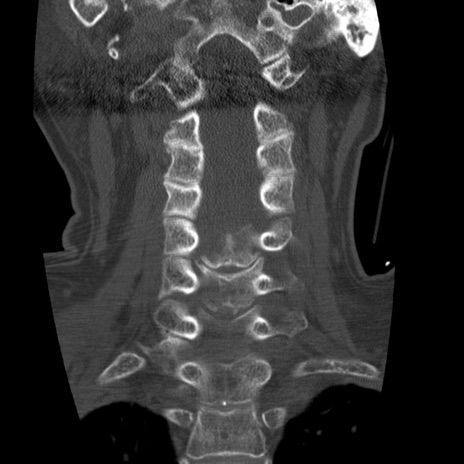

症例50 頚椎CT(冠状断像)

頚椎CT